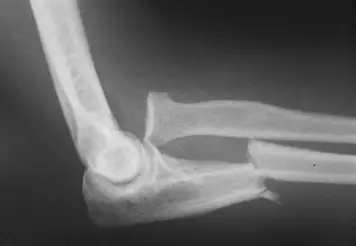

- 解剖位置:影像顯示為**肘關節(Elbow joint)**的側位(Lateral view)X光片,包含了肱骨遠端、尺骨近端與橈骨近端。

- 尺骨(Ulna):在尺骨近端骨幹(Proximal shaft)可見明顯的骨折線,且骨折斷端向掌側(Anterior/Volar)成角(Angulation)。

- 橈骨(Radius):橈骨頭(Radial head)與肱骨小頭(Capitellum)的關節對合關係異常。

- 正常情況下,無論X光片角度如何,沿著橈骨頸中心畫出的延伸線(Radiocapitellar line)應穿過肱骨小頭的中心。

- 本圖發現:橈骨頭向前方(Anteriorly)脫位,並未對準肱骨小頭。

- 綜合診斷:尺骨近端骨幹骨折合併橈骨頭脫位(Fracture of the proximal ulna with dislocation of the radial head)。

- 正確原因:影像特徵(尺骨斷、橈骨頭脫位)完全符合此定義。依據 Bado 分類法,橈骨頭向前方脫位屬於最常見的 Type I。

根據影像顯示的尺骨近端骨折合併橈骨頭前脫位,符合 Monteggia fracture 的定義,故最適當的診斷為 (D)。

- Type I (最常見):橈骨頭向前脫位,尺骨骨折向掌側成角(如本題影像)。